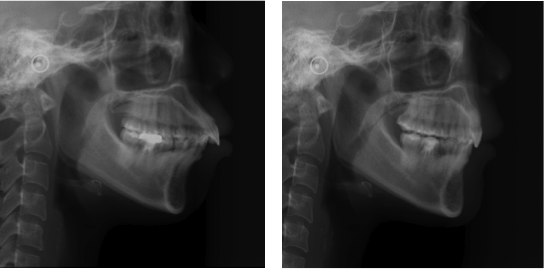

▼ 側面X光讓人無比震驚,前後變化更明顯

(陳煥文醫師案例分享)

圖片案例 牙齒矯正前後比對效果

這張比對圖更能明顯的看出來,只要牙齒後退,下巴變明顯,鼻子就更立體了!很神奇吧~ヽ( ^∀^)ノ